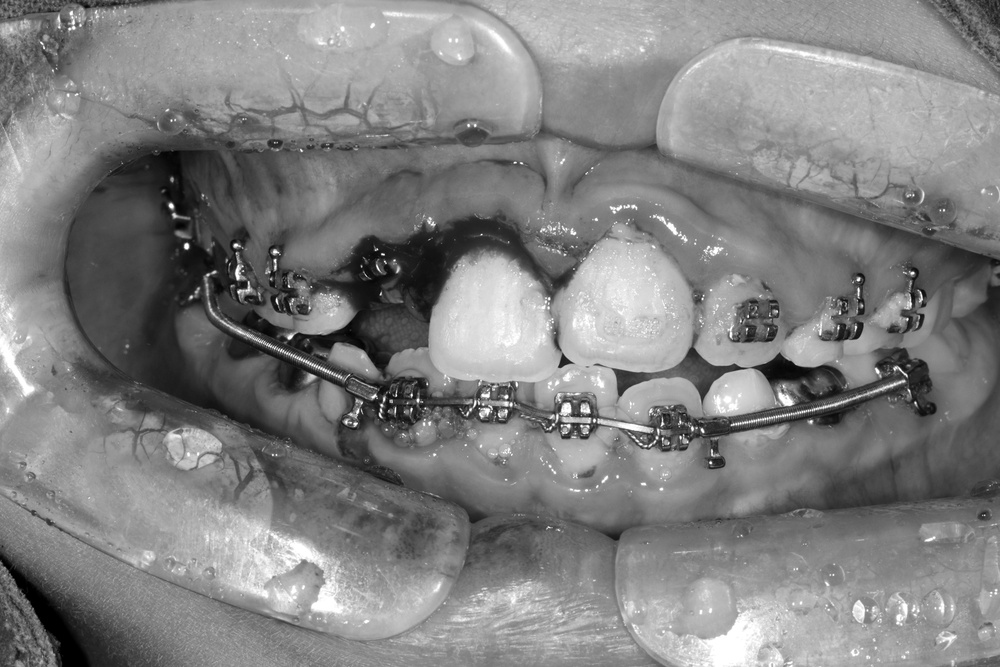

그런데 친구가 학교에서 부딪혀서 다쳐 왔습니다.

바로 처치(치아를 철사로 부목 고정)후 신경치료를 진행하였습니다.

이후 치아배열을 마무리하여 가지런한 이를 가지게 되었습니다.